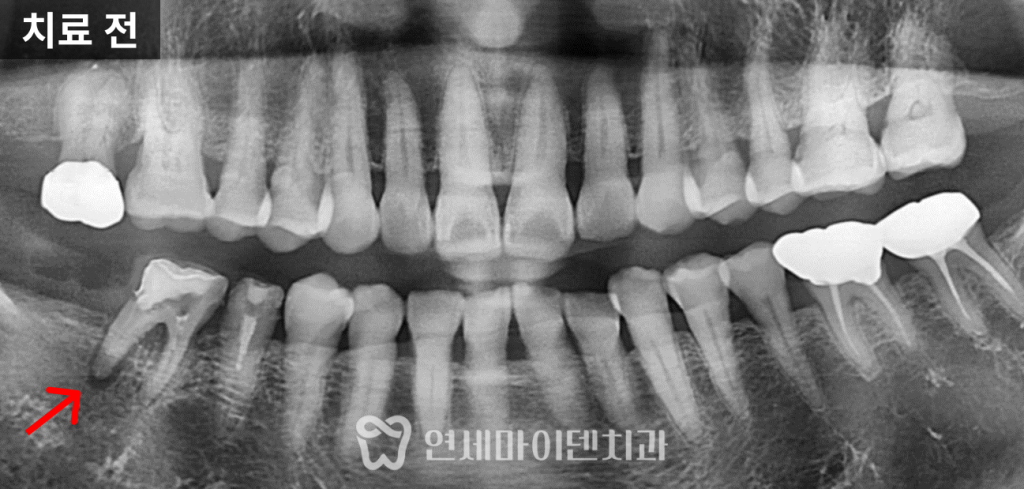

환자분은 오른쪽 아래 어금니 두 개에서

지속적인 염증과 통증을 호소하셨습니다.이미 신경치료를 한 상태였지만,

증상이 개선되지 않아 일상생활에도 불편을 느끼셨습니다.

파노라마 방사선 사진을 통해 상태를 확인한 결과,

앞쪽 뿌리는 비교적 건강했으나

뒤쪽 뿌리 주위의 치주 인대 공간이 넓어져 있었습니다.이는 염증으로 인해

뼈가 흡수되고 있다는 신호일 가능성이 높았습니다.이러한 소견을 바탕으로, 먼저 재신경치료를 시행하여